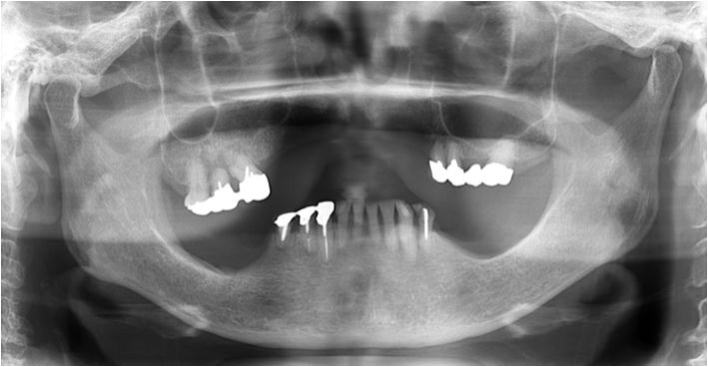

上の2枚のレントゲンは上下奥歯の咬合関係が無く左右前後の咬合崩壊が起きています。

この患者様は、〇 の歯以外は全て抜歯せざるを得ない状態でした。

歯がない箇所の放置は、咬合崩壊を必ず起こします。